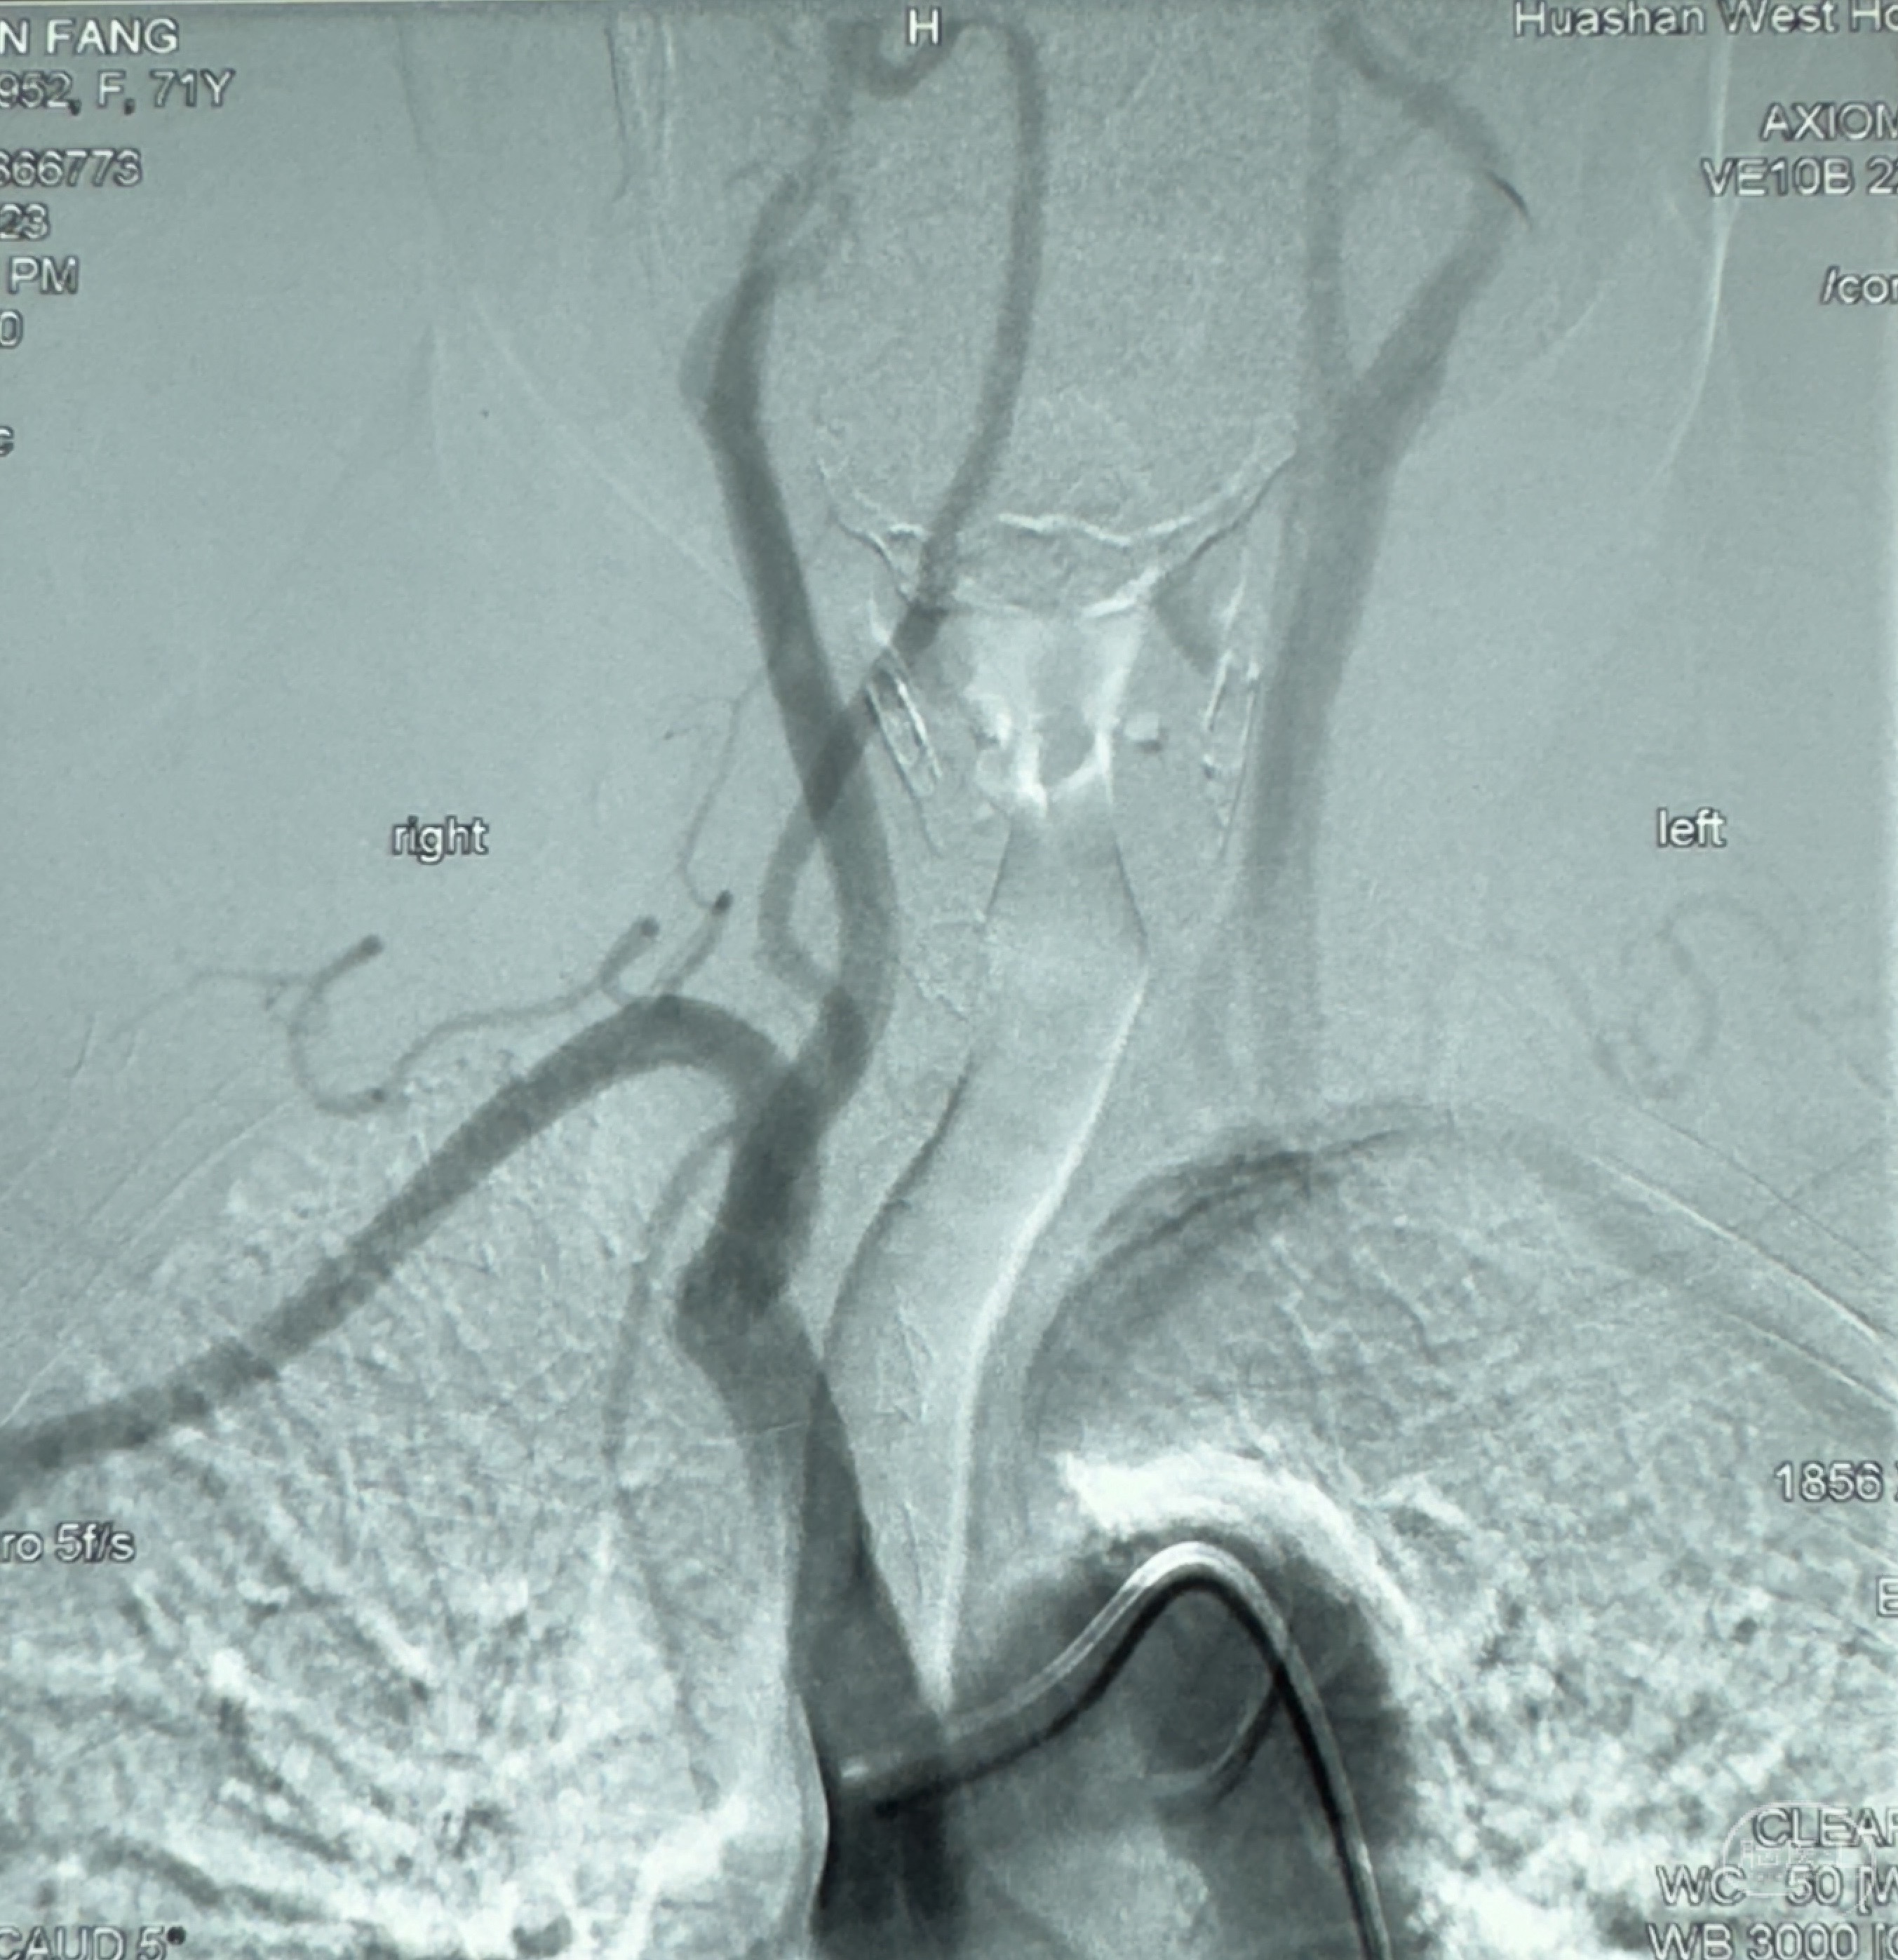

2023-12-27术后第十天复查DSA

支架贴壁佳,但可见射流,咋办?

2024-01-08全麻下再行植入密网支架一枚

Tubridge 4.5-35mm

支架植入顺利,贴壁佳,支架内血流通畅,动脉瘤内血液滞留明显